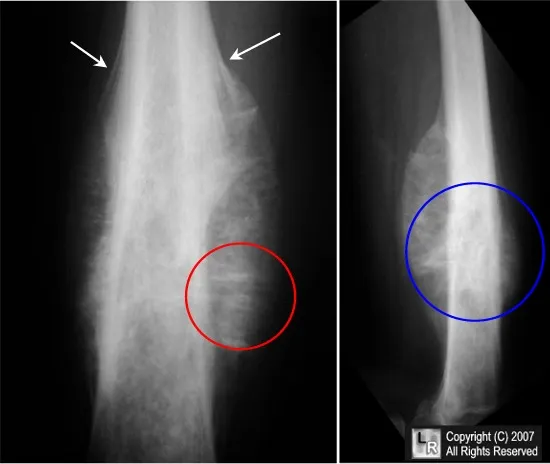

Ewing Sarcoma - Onion Skin Bully

- Site: Diaphysis of long bones (femur, tibia, humerus), pelvis, ribs.

- X-ray:

- Lytic lesion.

- 'Onion-peel' periosteal reaction (classic).

- 'Moth-eaten' appearance.

- Codman's triangle (possible).